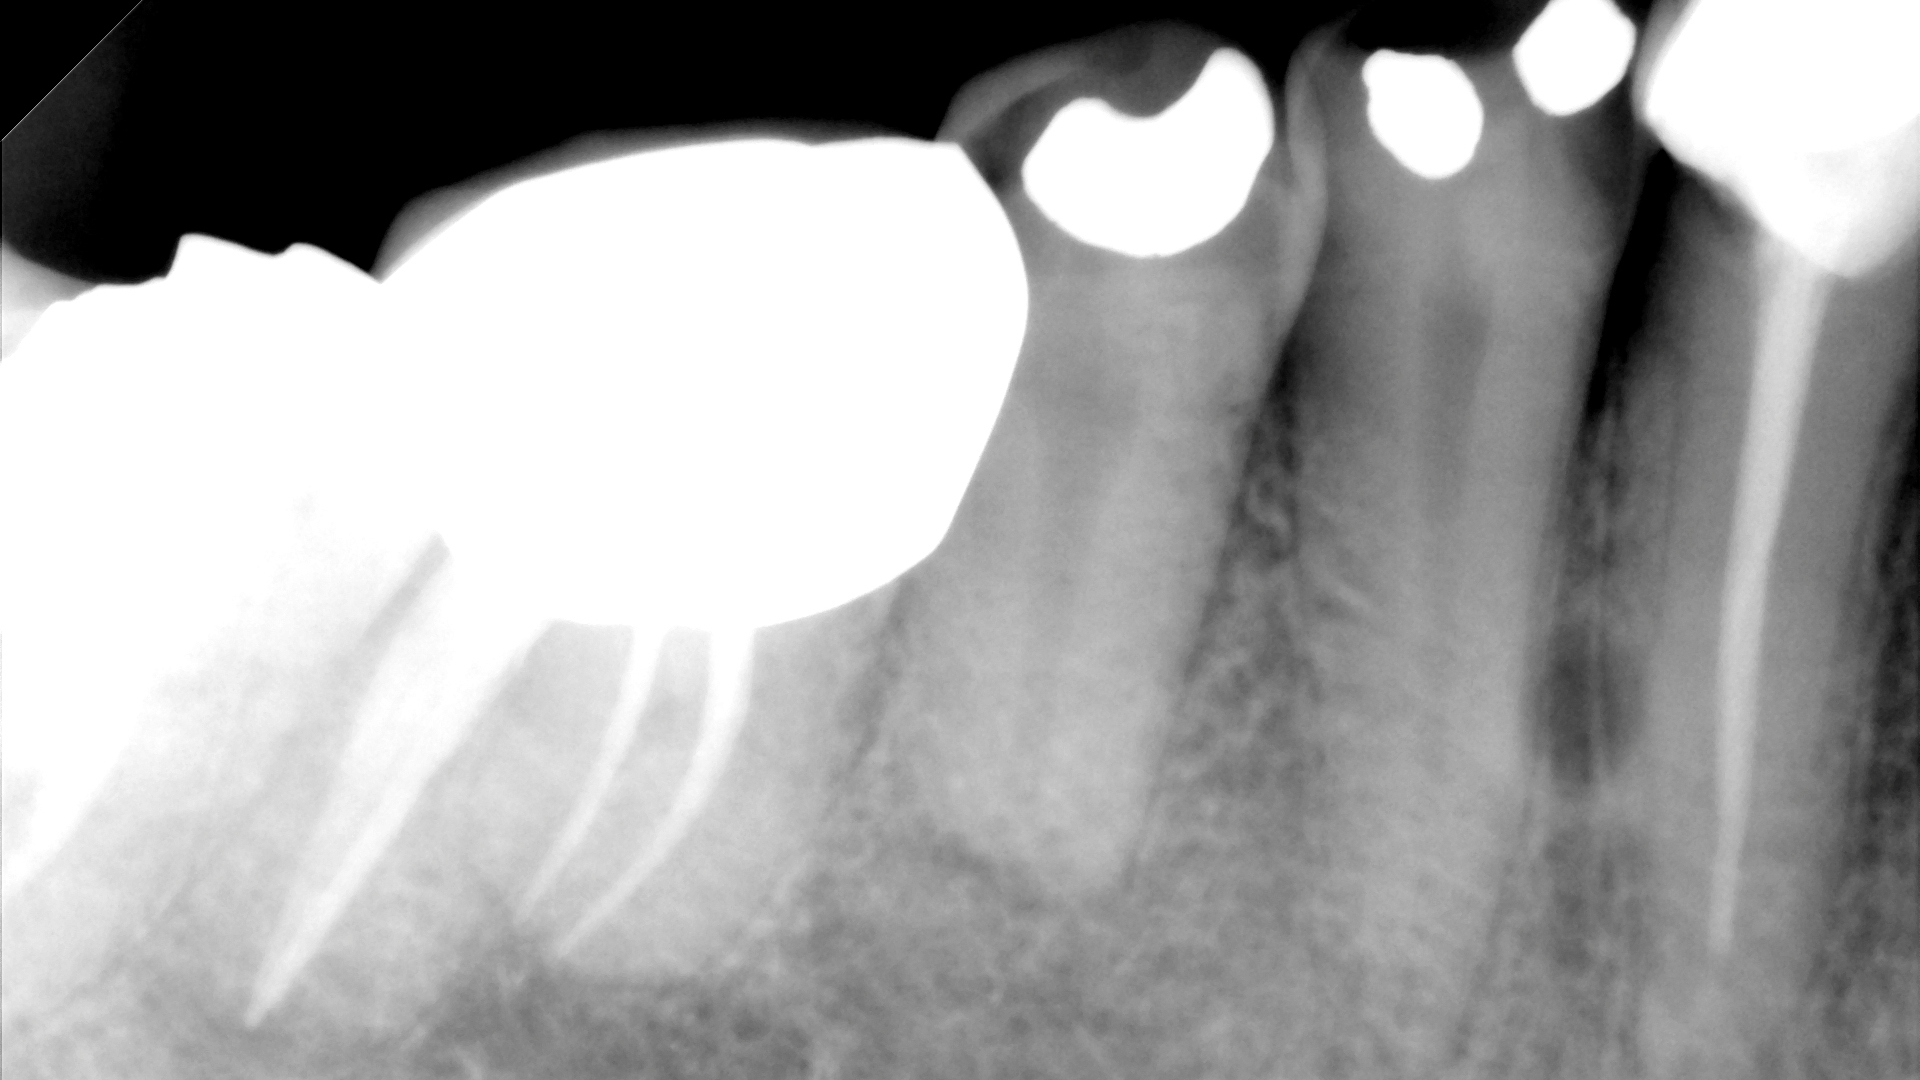

A complete mouth series was made with an incidental, well-defined, circular, radiolucent area noted between the roots of the mandibular right canine and first premolar.

For lateral periodontal cysts, there is a male predilection with a mean age of 50 years. They are typically asymptomatic and incidental findings. They are most commonly found between the lateral incisor and second premolar (mandible) and lateral incisor region (maxilla). The cyst appears as a well-defined, round/ovoid radiolucent entity. It may obliterate the lamina dura of adjacent teeth. As it enlarges, it may cause displacement and/or resorption of adjacent teeth. It is frequently single, but may be multiple. The size is typically less than 1 cm in diameter.

Differential interpretation includes keratocystic odontogenic tumor and lateral rarefying osteitis. Lateral rarefying osteitis will be associated with a nonvital tooth. The only way to determine the difference between a lateral periodontal cyst and a keratocystic odontogenic tumor is with histopathological diagnosis. Treatment is surgical excision.